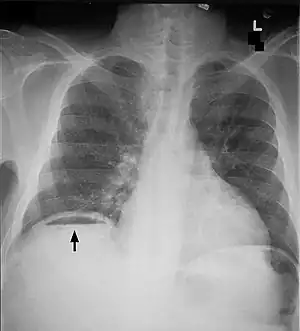

O diagnóstico é habitualmente realizado pela radiografia (tórax e abdome), sendo o achado mais freqüente a presença de ar intraperitoneal no quadrante superior direito do abdome. O pneumoperitônio torna-se radiologicamente evidente quando a quantidade de ar no abdome oscila entre 30–90 cm.

Pode-se observar na radiografia o sinal de Rigler, que é a visualização das paredes dos intestinos. No exame físico pode-se observar o sinal de Jobert, que é o aparecimento de hipertimpanismo na região hepática.